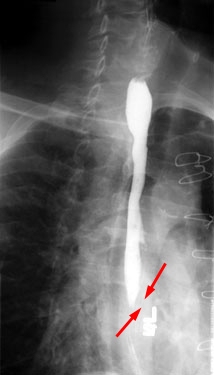

|

Esophageal

strictures are areas of local esophageal narrowing. They can result from

ingestion of corrosive agents, previous esophageal atresia repair, epidermolysis

bullosa or gastroesophageal reflux. A commonly used therapy is using balloon catheters

under fluoroscopic guidance to dilate the esophagus. |